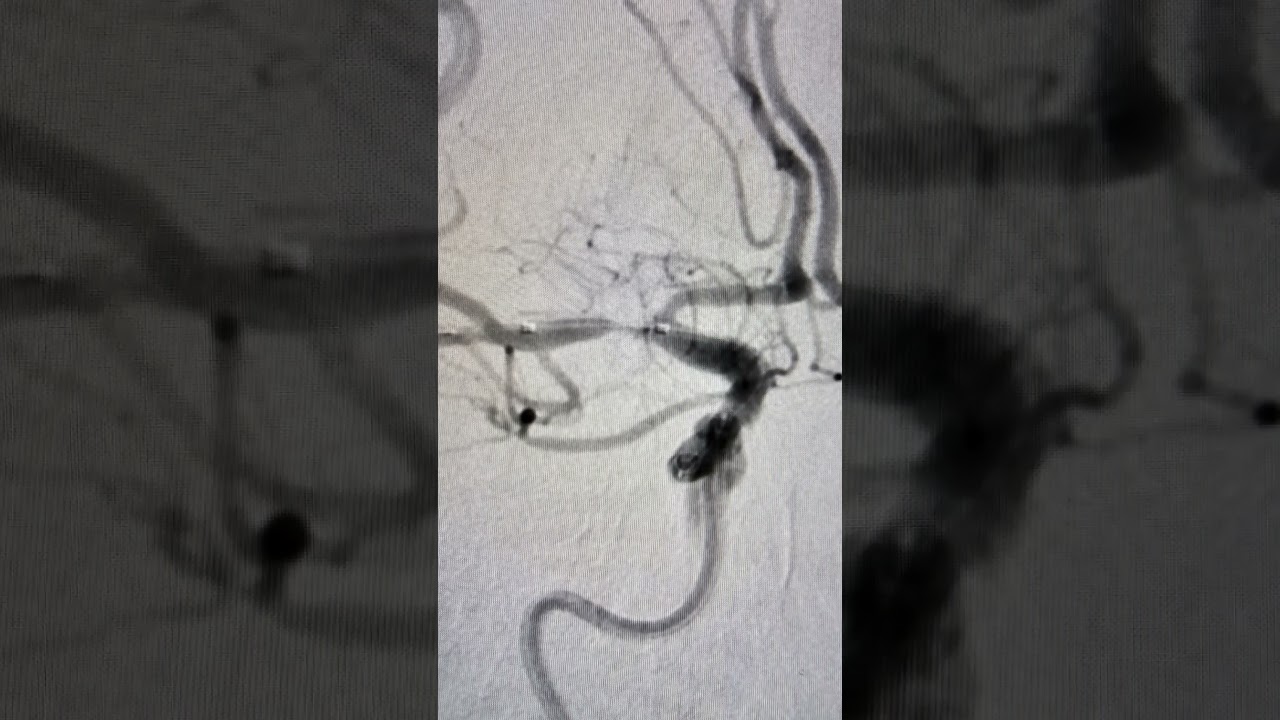

Angiografia diagnóstica

Considerada padrão ouro, a angiografia cerebral é um procedimento médico incrível e minimamente invasivo que utiliza cateteres e raios X para avaliar a anatomia e a circulação nos vasos sanguíneos do cérebro. Ela é extremamente útil para investigar condições que afetam os vasos sanguíneos do cérebro e do pescoço. O exame é detalhado e fornece uma visão interna e altamente acurada dos vasos sanguíneos, permitindo a identificação de anormalidades como aneurismas, estenoses de carótidas e vertebrais, fístulas arteriovenosas e malformações arteriovenosas. É um procedimento minimamente invasivo e apresenta um risco extremamente baixo, tornando-se uma ferramenta valiosa na medicina moderna.